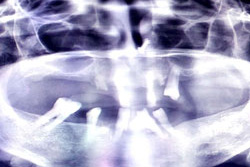

Before Treatment

OPG (Pre Treatment)

After Areatment

OPG (Post Treatment)

Case of full mouth rehabilitation All teeth extracted Upper single complete denture and lower Implant supported denture